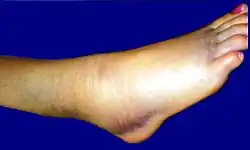

При растяжении связок голеностопного сустава быстро развивается отек вследствие кровоизлияния с внутренней или наружной стороны сустава, появляются резкие боли при подвертывании стопы внутрь. При пальпации под лодыжками ощущается резкая болезненность. Если одновременно с растяжением связок происходит перелом V плюсневой кости, то определяется резкая боль при пальпации её основания.